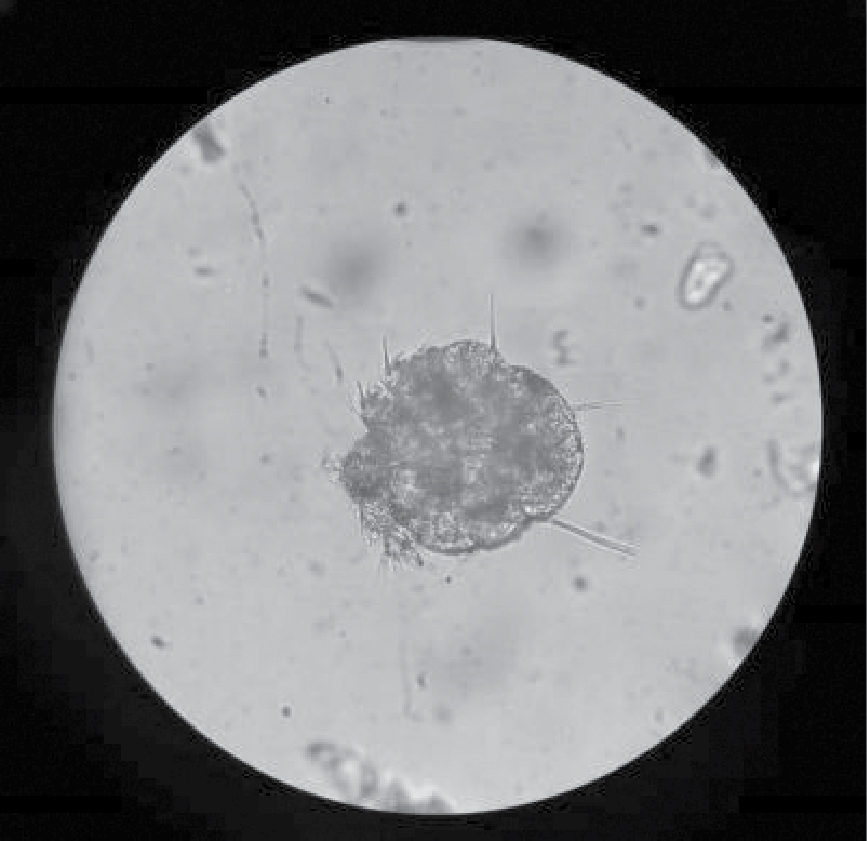

Differential diagnosis included psoriasis, severe seborrheic dermatitis and eczema. Due to the involvement of interdigital spaces and keeping in mind the long duration of disease unresponsive to topical or oral steroids, scabies was also kept as a differential diagnosis and scraping of the skin was taken from the lesions on the patient’s elbows and web spaces of the hands and nails. Scrapings were processed and prepared with 10% potassium hydroxide. On direct microscopic examination, a number of mites were seen (Fig. 4), hence confirming our diagnosis.

Figure 4. Mite of Sarcoptes scabiei from lesion scraping.